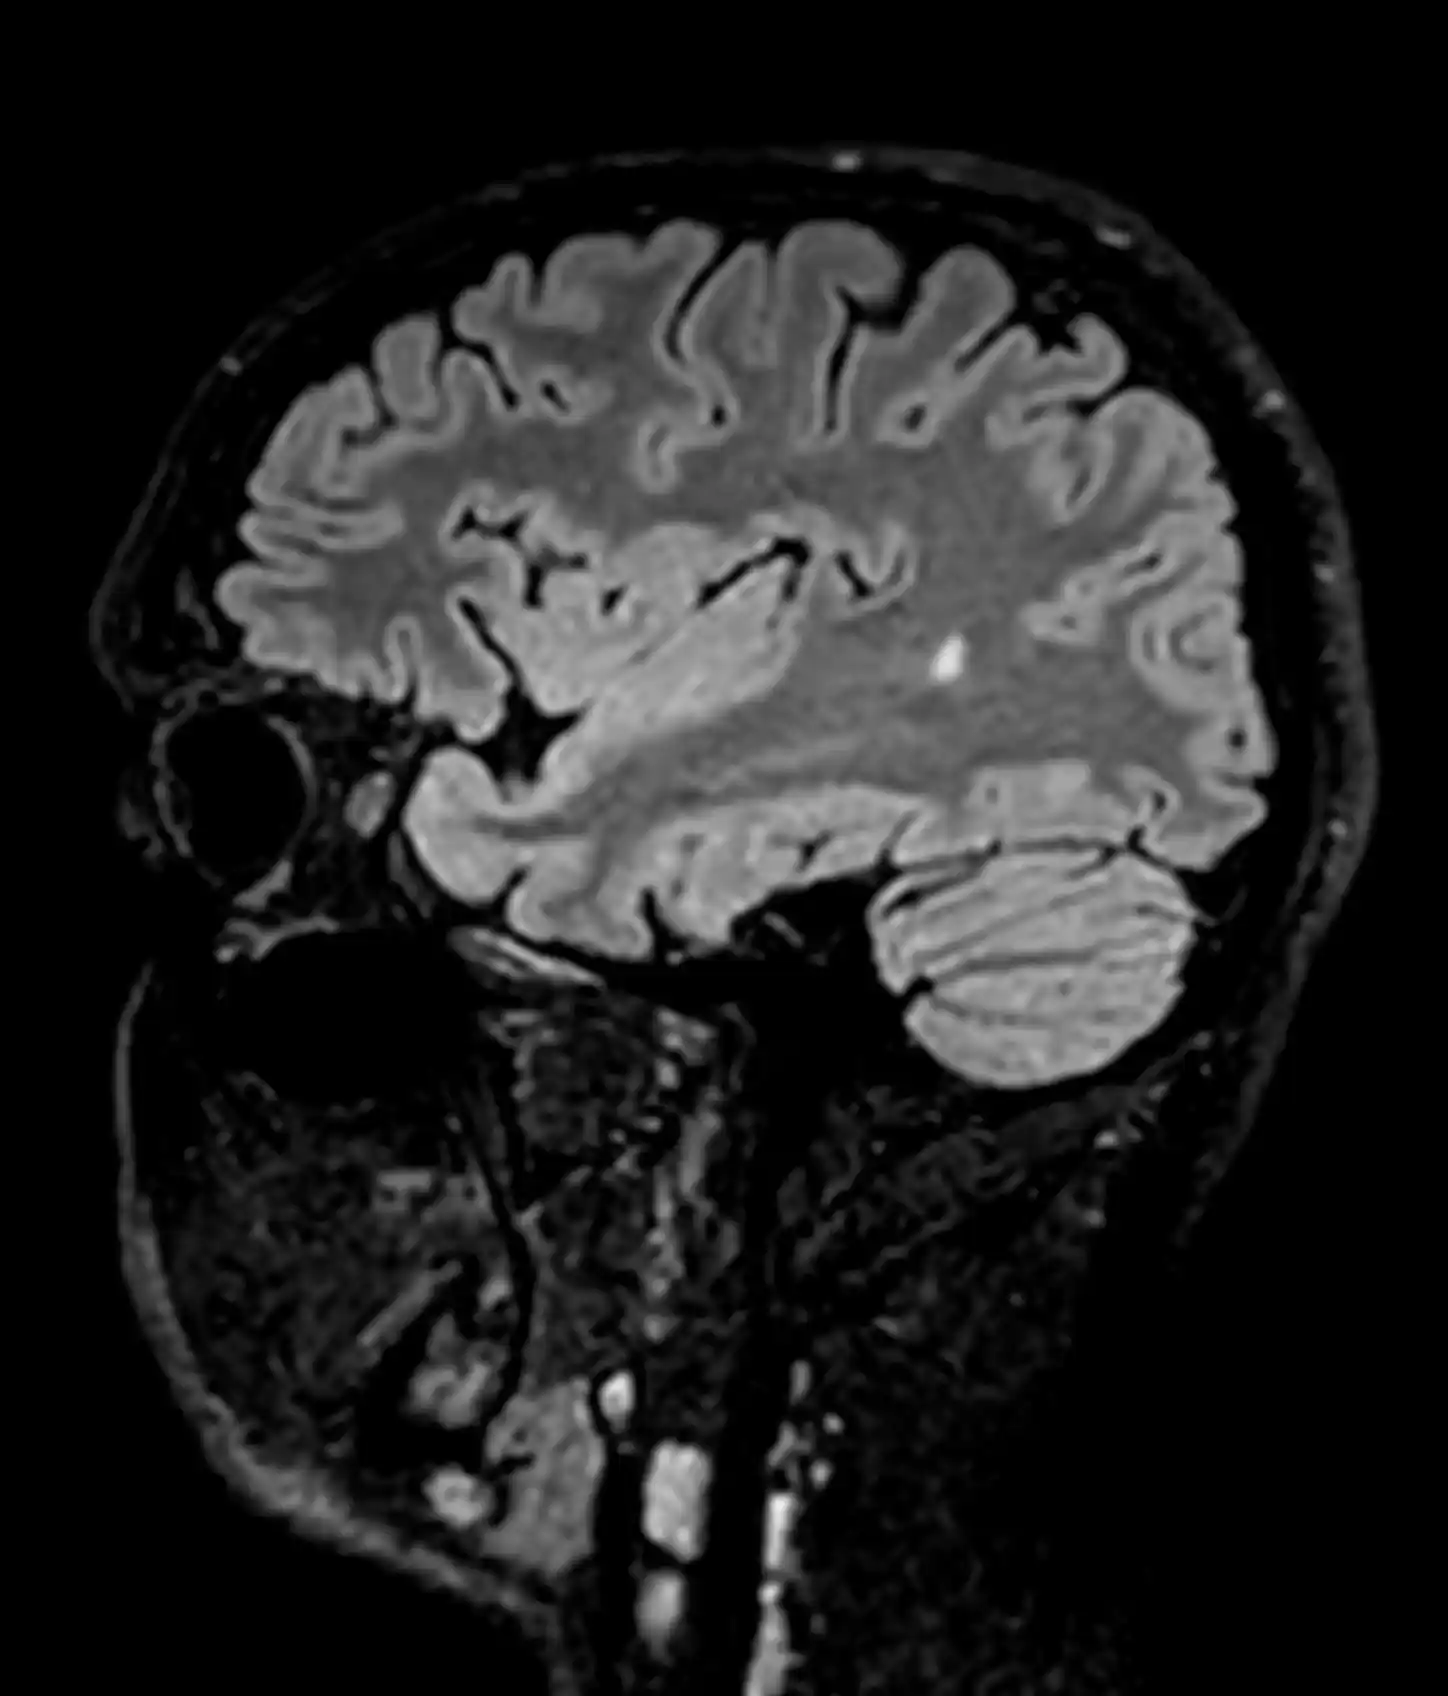

У центрі встановлено інноваційний МРТ Philips Ingenia 1.5T, оснащений технологіями штучного інтелекту (AI), що забезпечує високу точність зображень та дозволяє виявляти патології навіть на ранніх стадіях.

У центрі встановлено Philips Ingenia 1.5T — один із найсучасніших МРТ-апаратів у світі.

Наші можливості МРТ

У центрі проводяться МРТ-дослідження:

- головного мозку

Сучасні можливості МРТ дозволяють виявляти захворювання на ранніх стадіях.